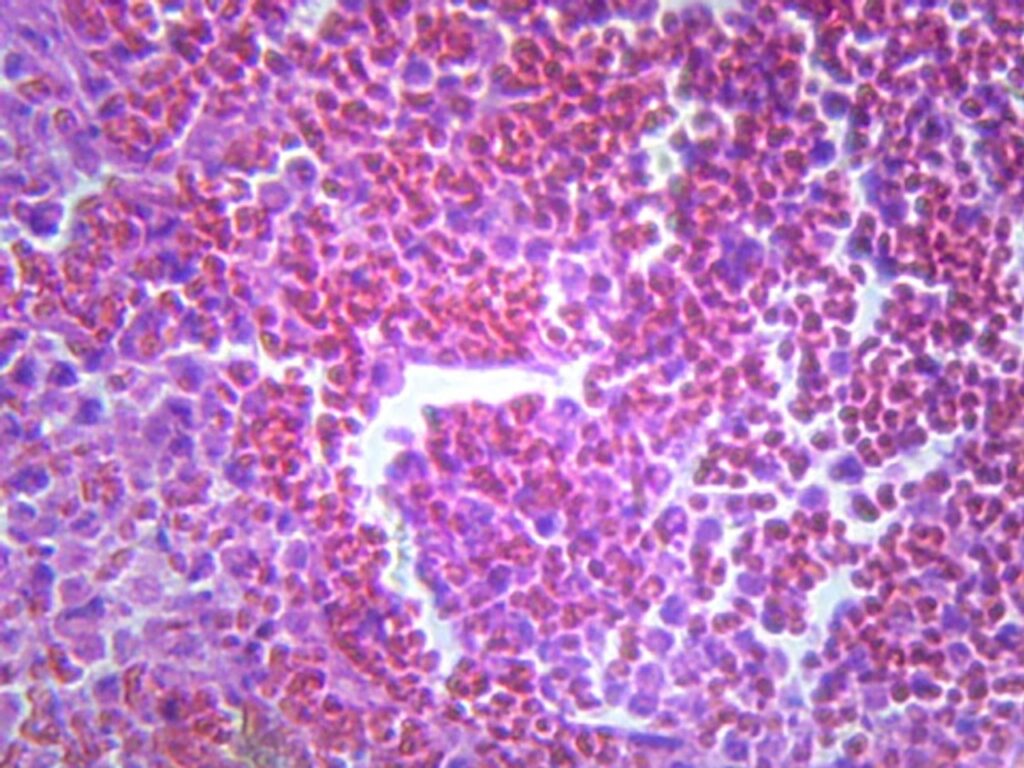

Den mest grundlæggende og udbredte farvning er Hæmatoxylin & Eosin (H&E). Hæmatoxylin farver cellekerner blå-lilla, mens Eosin farver cytoplasma og bindevæv i forskellige nuancer af pink. H&E-farvning giver et fantastisk overblik over vævets generelle arkitektur og afslører inflammationens mønster, tilstedeværelsen af nekrose, hyaline membraner eller granulomer. For at identificere specifikke årsager er specialfarvninger dog ofte nødvendige.

| Hæmatoxylin & Eosin (H&E) | Standardfarvning for overblik | Cellekerner (blå), cytoplasma/bindevæv (pink) |